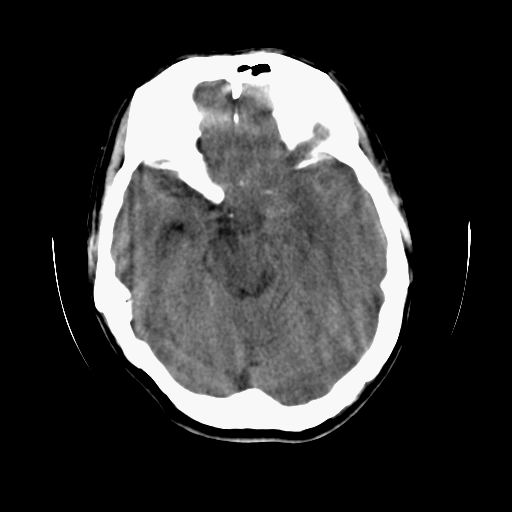

标题: CT13217:头部外伤三月余,头痛三天 [打印本页]

标题: CT13217:头部外伤三月余,头痛三天

左侧慢性硬膜下血肿

太典型,左侧慢性硬膜下血肿

左侧慢性硬膜下血肿,大脑镰下疝。

支持左额颞顶慢性硬膜下血肿伴大脑镰下疝。

血肿是急性、亚急性、还是慢性,要结合外伤时间考虑的,本例头部外伤三个月,应该是明显的慢性硬膜下血肿,但血肿的等密度显然不符合病理改变,估计是合并再次出血,中线结构移位明显,有脑疝形成。应穿刺减压。

血肿是急性、亚急性、还是慢性,要结合外伤时间考虑的,本例头部外伤三个月,应该是明显的慢性硬膜下血肿,但血肿的等密度显然不符合病理改变,估计是合并再次出血,中线结构移位明显,有脑疝形成。应穿刺减压。 大于2个月为慢性出血,2周到二个月为亚急性出血